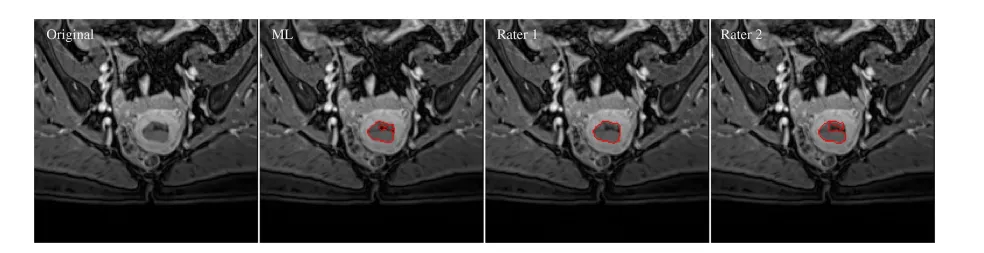

2. Figure 2:2D肿瘤轮廓分割一致性

红色实线为AI、专家1、专家2的肿瘤分割轮廓,叠加在MRI VIBE序列图像上; -

量化结果:DSC_ML,R1=0.96、DSC_ML,R2=0.89、DSC_R1,R2=0.90,AI与专家轮廓重合度极高。